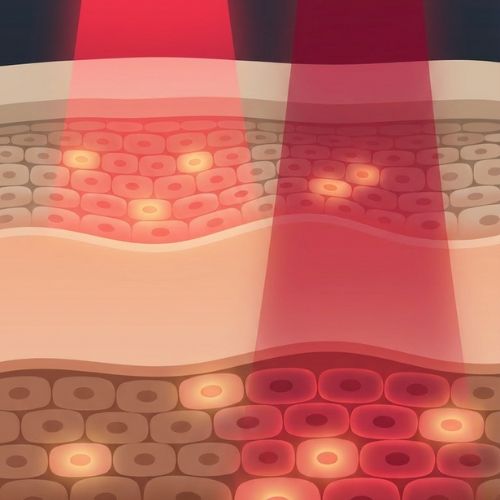

Red light therapy (also known as photobiomodulation) uses specific wavelengths of light to stimulate your cells' natural repair processes. Red light (660nm) targets surface tissue and inflammation, while near-infrared light (850nm) penetrates deeper — reaching joints, muscles, and bone-level structures. It's non-invasive, drug-free, and backed by over 3,000 published studies.

The mat delivers 1,370 clinical-grade LEDs across your entire body while you lie down. The dual wavelengths (660nm + 850nm) are absorbed by your cells, boosting mitochondrial ATP production — your body's natural repair fuel. Over time, this calms inflammation, eases stiffness, and accelerates recovery.

Pavra uses the same clinically studied wavelengths (660nm + 850nm) shown in published research to reduce inflammation, ease joint pain, and support tissue repair. Many of our customers with arthritis, fibromyalgia, and chronic joint conditions report significant improvement with consistent daily use. Results vary, and we always recommend consulting your doctor alongside any new therapy.

Absolutely. Photobiomodulation — the science behind red and near-infrared light therapy — has been studied in over 3,000 peer-reviewed publications. The wavelengths Pavra uses (660nm and 850nm) are the most widely researched for inflammation, pain reduction, and cellular repair. This isn't new or experimental — it's been used in clinical and research settings for decades.